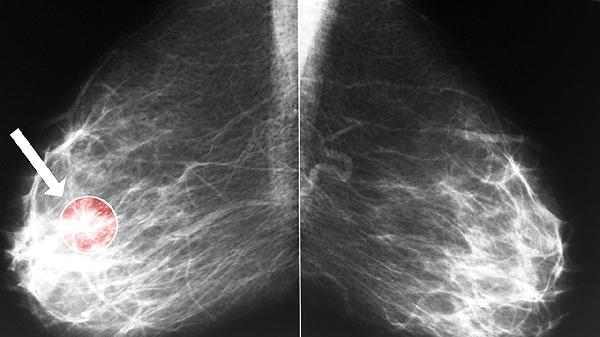

消癌平分散片的主要成分是从萝藦科植物通关藤提取的抗肿瘤活性物质,具有抑制肿瘤细胞增殖、诱导凋亡的作用。临床观察显示,对于肺癌、肝癌、胃癌等实体肿瘤,部分患者用药后可出现病灶稳定或缩小的现象,同时能改善化疗引起的白细胞减少、乏力等症状。该药联合常规放化疗使用时,可能帮助减轻恶心呕吐、骨髓抑制等不良反应。